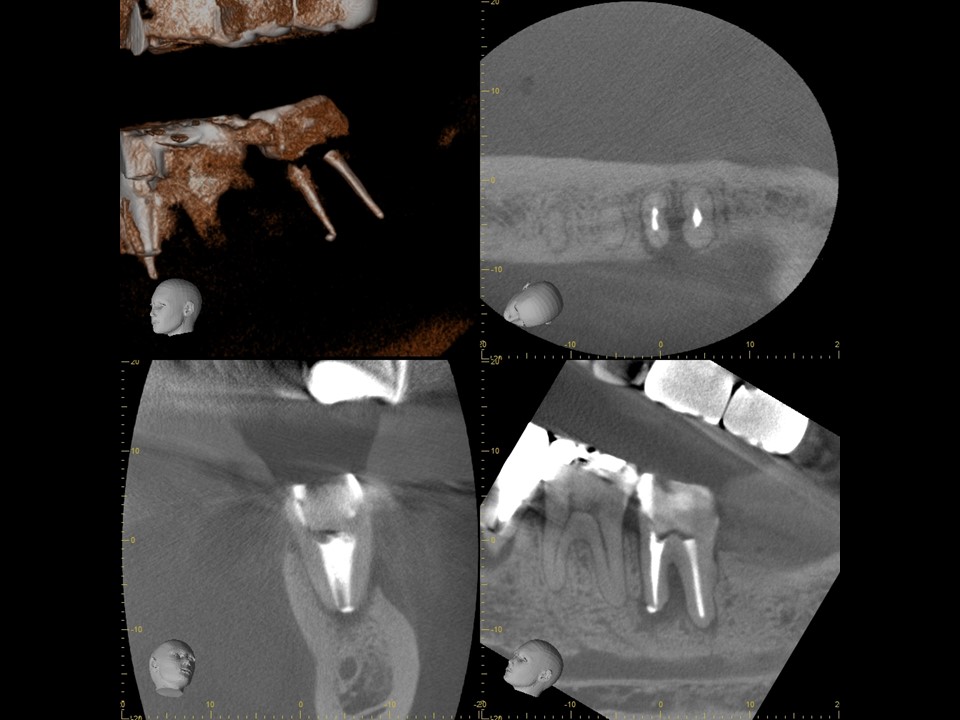

診断と治療計画の立案

当該の左下7番の奥歯はクラウンで被せてありましたが、頬側に歯茎の腫れ(フィステル、サイナストラクト)を認めました。レントゲンおよびCTによる診査を行ったところ、すでに根管治療が施してあるものの根管充填が不十分で、根尖病変を生じていました(下写真)。また、歯根の先端部分にはファイルと思われる器具の破折片を認めました(矢印)。根管内部へのバクテリアの感染による慢性化膿性根尖性歯周炎と診断し、再根管治療をおこなうことにしました。

治療前レントゲン | 治療前CT |

---|---|

治療前レントゲン |

---|

治療前CT |

治療前のレントゲンおよびCT画像です。当該歯はすでに根管治療が施してあり、根尖部には根尖病変によるX線透過像を認めます。

また、根尖部にはファイルと思われる器具の残存を認めます(矢印)。

ガッタパーチャを除去したところです。CT画像にて根尖部に破折しているファイルが残っているのが確認できます(矢印)。

根管充填後のレントゲンおよびCT画像です。根尖までしっかりとお薬が詰まっていることが確認できます。